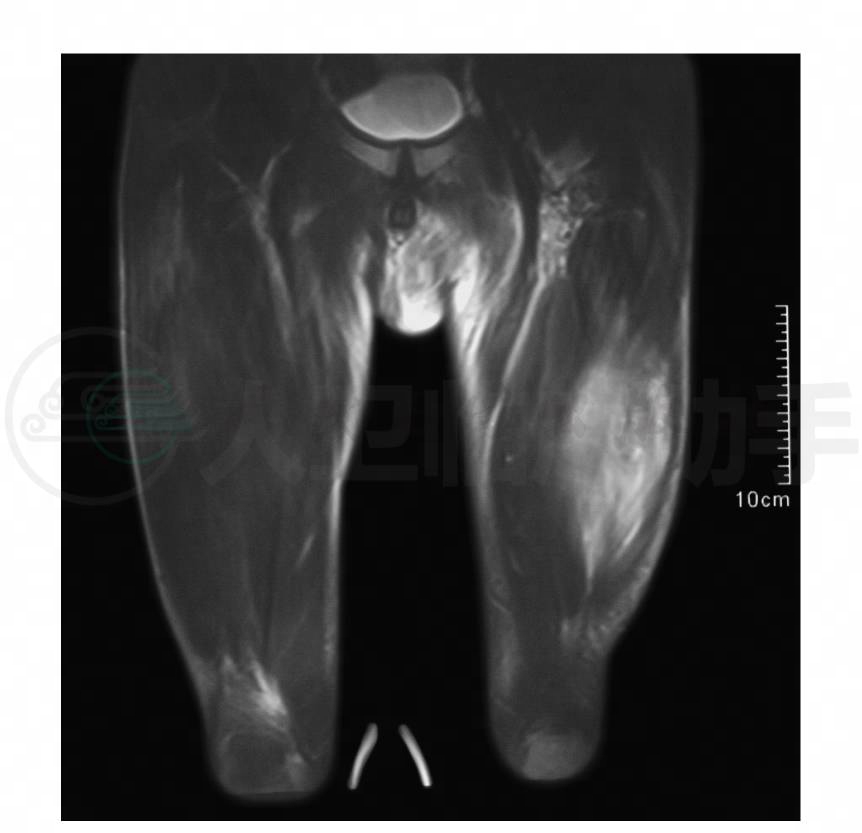

2.双股肌肉骨骼MRI检查

显示双侧股软组织弥漫性T1WI低信号、T2WI高WI高信号,考虑炎性病变(图2)。

图2 双股软组织弥漫性T1WI低信号、T2WI高信号